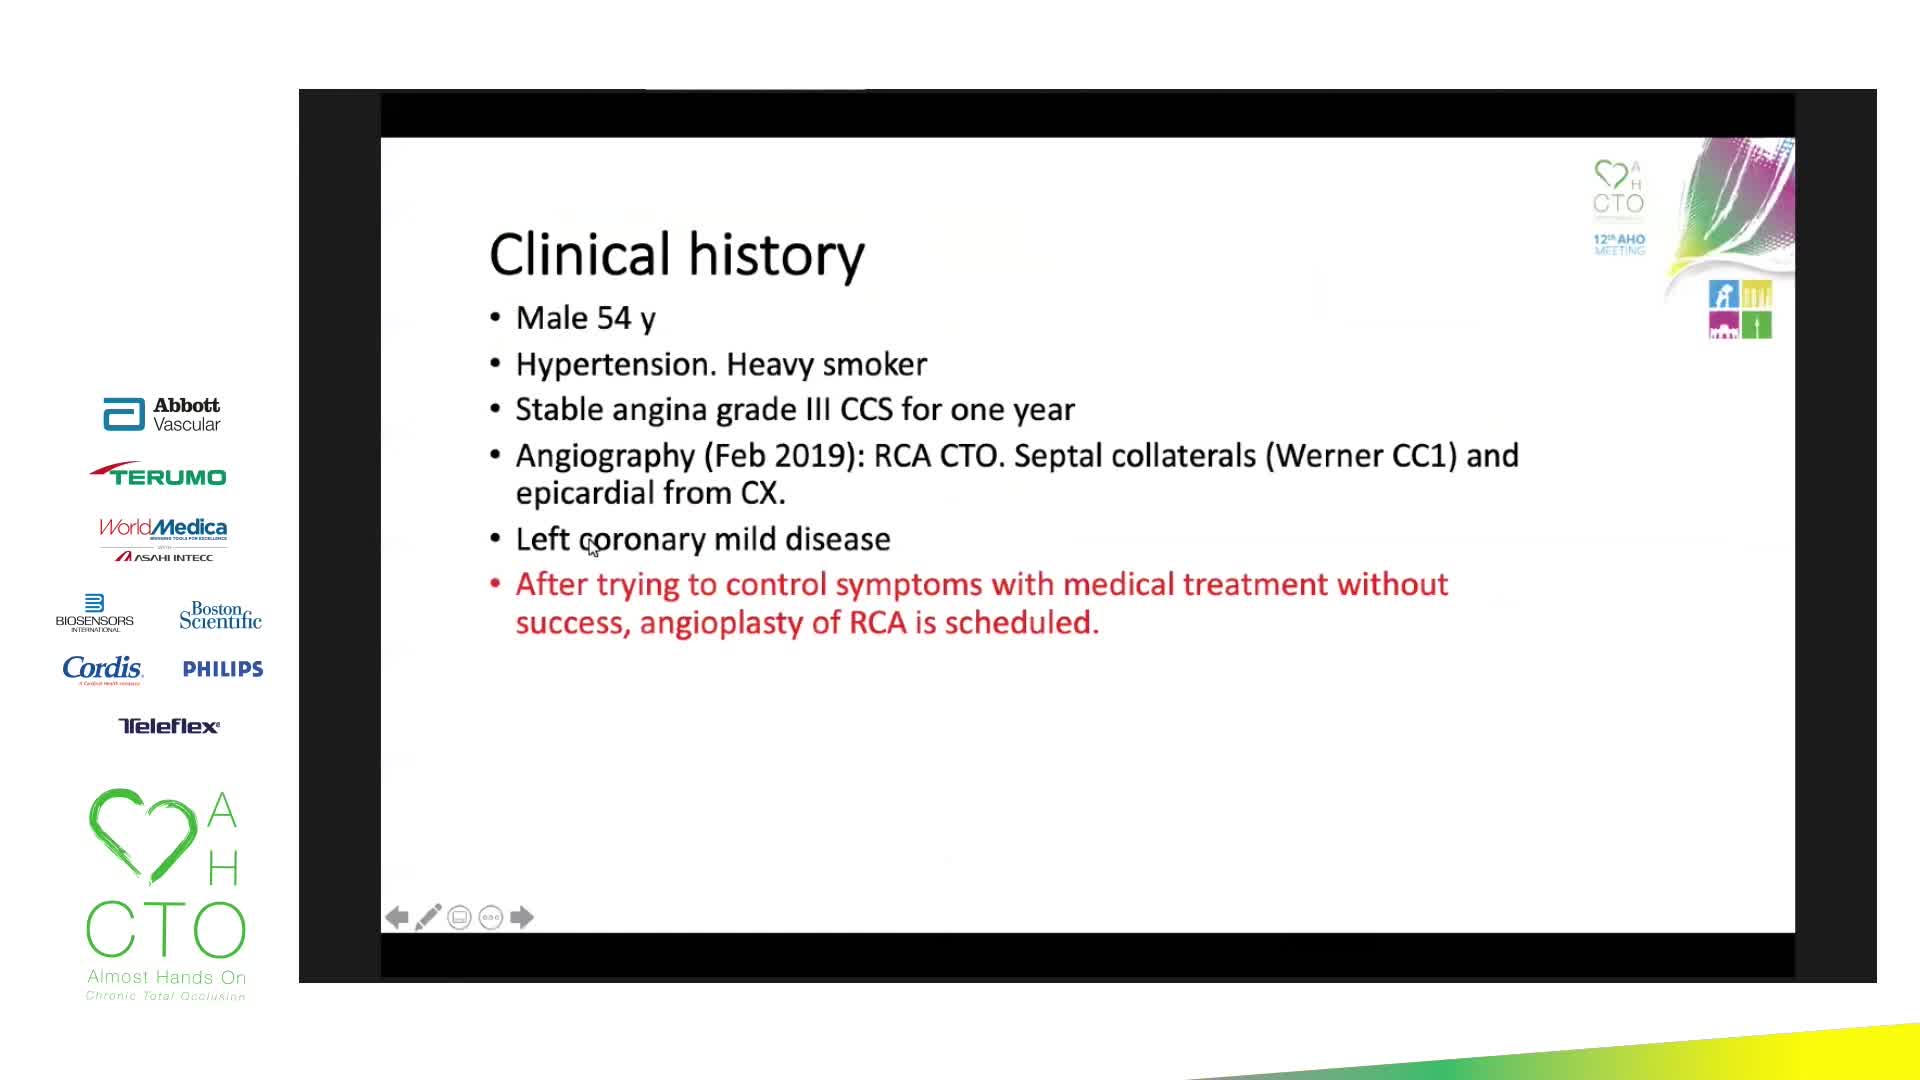

12th AHO meeting December 2020